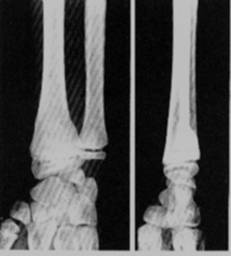

1. Traumatisme – fracturi

- la nivelul membrelor apar forme specifice copilariei:

■decolarea epifizara care poate fi:

- pura (cu smulgerea totala a ligamentelor epifizare si epifiza dislocata), - asociata cu fractura parcelara metafizara,

- asociata cu fractura epifizara,

- fractura metafizo-epifizara ce traverseaza cartilajul de crestere,

- traumatism in axul lung al osului cu turtirea cartilajului de crestere.

Fig. 112 -    Fractura in lemn verde

Fig.    113 - Fractura subperiostala

■fractura in lemn verde in care indoirea traumatica a osului duce prin flectare, la o linie de fractura incompleta sau denivelare corticala marginala la nivelul convexitatii;